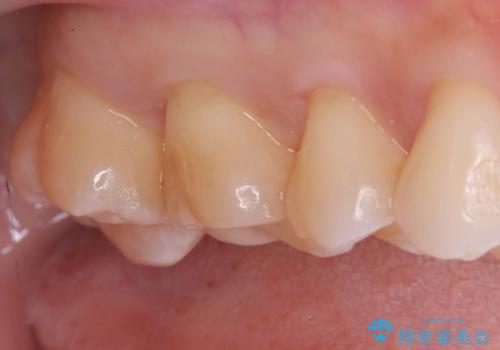

【セラミックインレー】咬合面のカリエス

- メンテナンス時に見つかった虫歯です。二次カリエスのリスクを下げる為に虫歯を除去後セラミックインレーで治療を行いました。

咬合面の溝が深く虫歯のリスクが大きい患者様です。

他の歯も咬合面に同じように虫歯ができて大きくなってしまった経験があることから今回は大きくそして深く進行する前に虫歯を除去しセラミックインレーで治療を行いました。